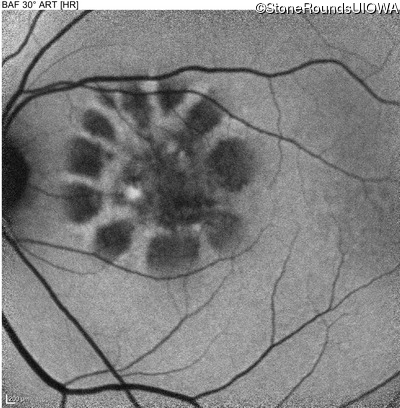

Best Disease (IIB)

Age at visit: 51 years

Age at visit: 52 years